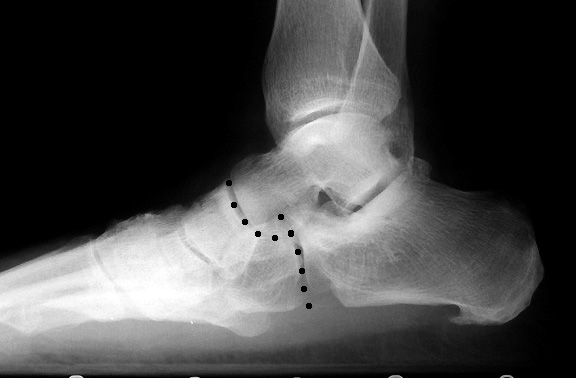

Carrying angle of the elbow. B abduction of the midfoot and pronation of the forefoot is also seen with inward collapse of the ankle joint resulting in rotation of the forefoot away from the center axis. An angle greater than 4 degrees convex upward is considered a pes cavus 10 11. Pes planus in contradistinction will show 7.

Loss of the normal straight line relationship with mearys angle 40 convex downwards. Different parameters have been described to assess talar head uncoverage including the anterior talus first metatarsal angle normal 00 to 200 talonavicular coverage angle normal70 talonavicular uncoverage percent normal 10 to 30 and lateral incongruency angle normal 50260. For example a s hoe insert used for the flat foot is designed based on the degree of flatness. Flat feet also called pes planus or fallen arches is a postural deformity in which the arches of the foot collapse with the entire sole of the foot coming into complete or near complete contact with the ground.

Syndesmosis rid6088 injury. A pediatric pes planus results in hindfoot valgus as defined by the angle formed by the leg and heel. 10 200 indicative of pes planus when 180. In normal feet the relationship between the talus and the 1 st metatarsal results in a straight line being formed along their axes ie.

It is a measurement that reflects the height of the foot framework but is affected by abnormal pronation or supination of the foot. Normal mearys angle 00.